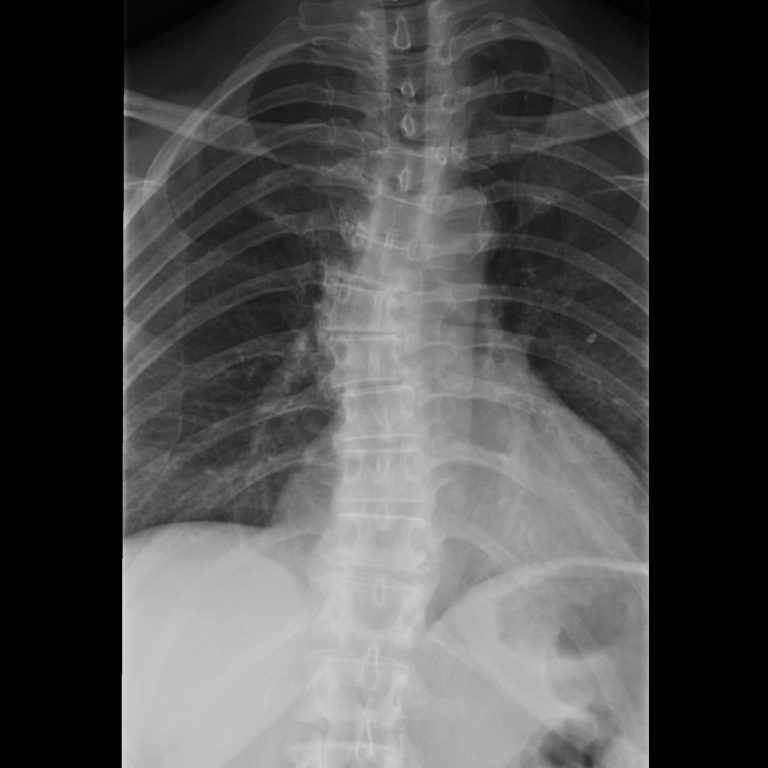

Unfälle

Unser Team ist spezialisiert auf die Diagnose und Behandlung von Sportverletzungen, Arbeits- und Schulunfällen, Schnitt- und Platzwunden, Knochen- und Wirbelbrüche sowie die Nachsorge nach Operationen.